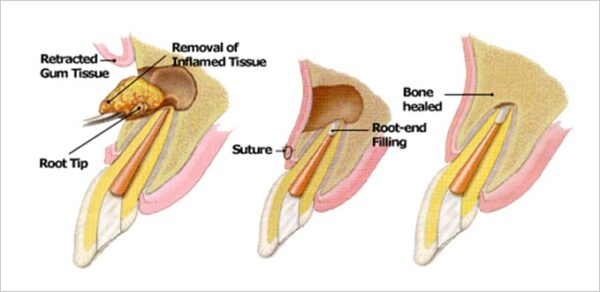

【歯根端切除術とは?】

歯の根の先にできた膿の袋およびその感染源を外科的に取り除く治療法です。

歯の根の先端を切除し、マイクロスコープ(歯科用顕微鏡)を用いて切断面を拡大観察します。その上で、根の先から逆方向に清掃・充填を行います(逆根管形成・逆根管充填)。

【歯根端切除術の流れ】

① 歯ぐきを開き、根の先を確認する

② 根の周囲の炎症組織を除去する

③ 根の先端を約3mm切除する

④ マイクロスコープで切断面を精査し、感染源の有無を確認する

⑤ 根管内の材料を約3mm除去し、生体親和性の高い材料(MTAセメント:封鎖性に優れた歯科材料)を充填する

⑥ 歯ぐきを戻して縫合する

【術後の経過】